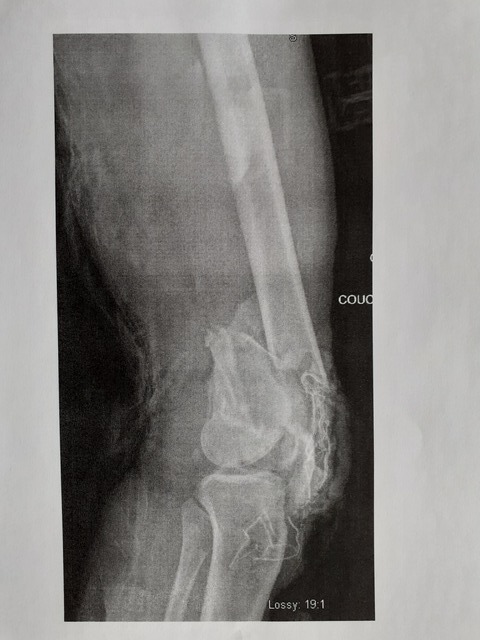

genou

Image

Pour le cliché radio de ta jambe, putain, j'étais au café-tartine du matin :lol:

désolé pour la tartine, -d'ailleurs j'ai peut-etre oublié de preciser que la 1ere radio c'est le genou, et la 2eme le bras^^